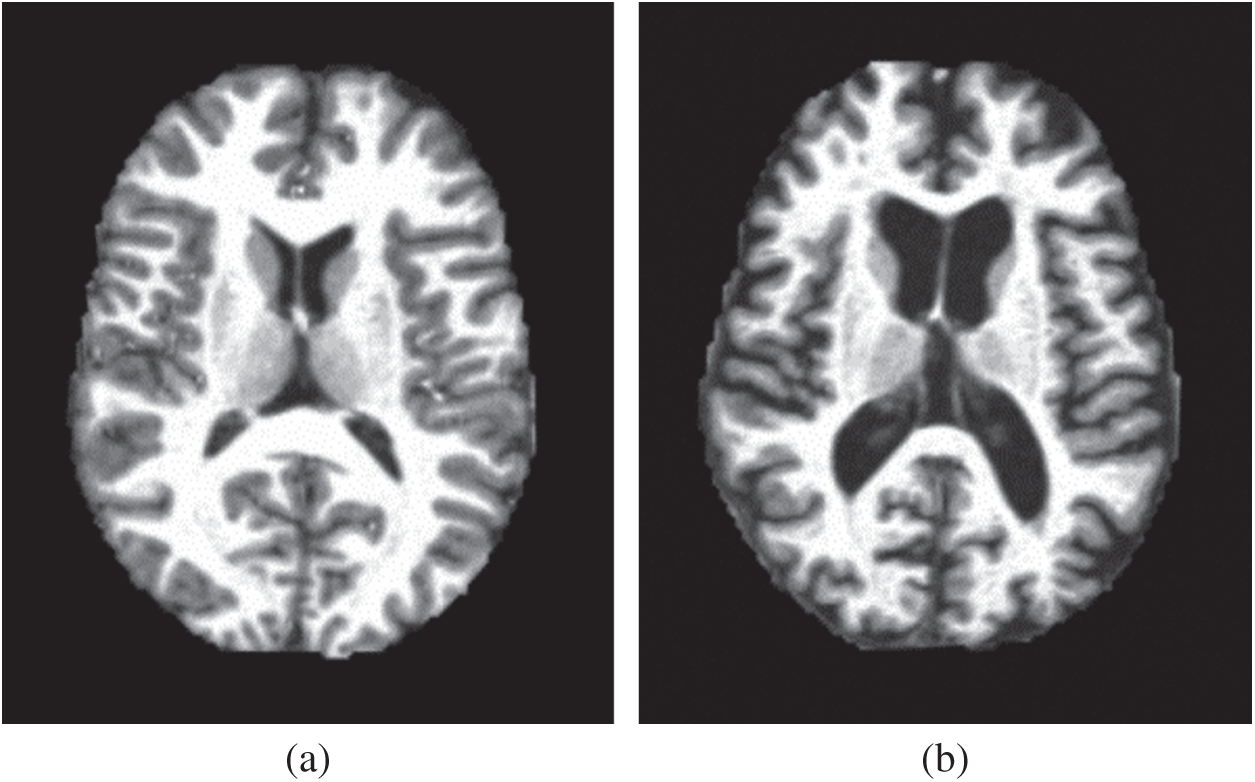

Our method first obtains the image features of the magnetic resonance imaging (MRI) data in a higher-dimensional space through wavelet energy entropy, then the hyperplane of linear classification is used to separate the positive and negative samples, and establishes the model of the relationship between variables by linear regression. Finally, the 10-fold cross-validation is used to calculate the mean and standard deviation to verify the performance of the constructed model. Figs. 1a, 1b show two samples of the healthy brain and an alcoholic brain.

Figure 1: Two samples of our dataset (a) Healthy brain (b) Alcoholism brain